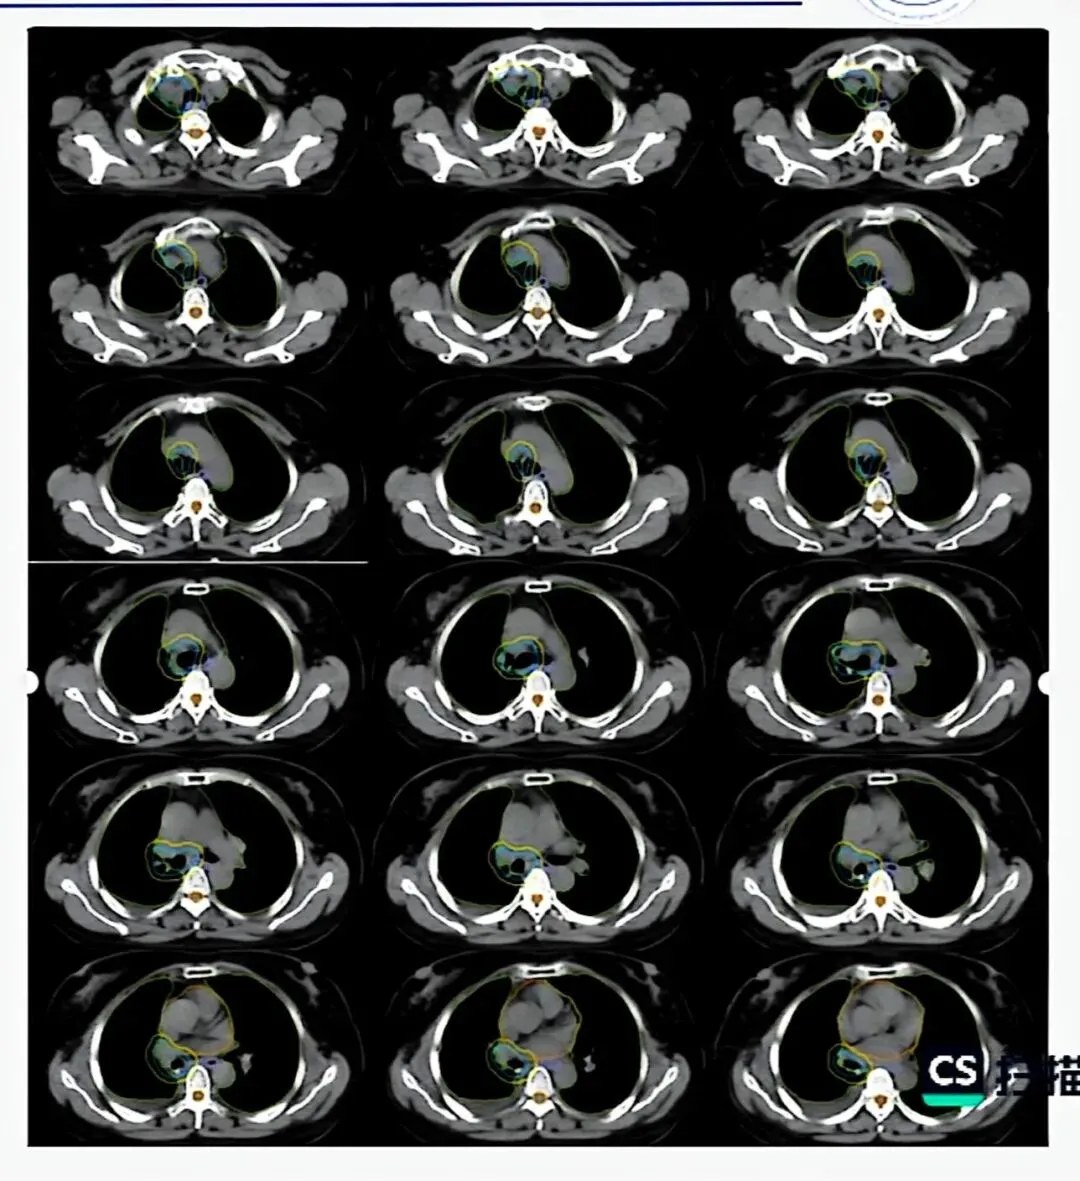

四、靶区勾画:从理论到实践

1. ICRU靶区定义体系

GTV(肿瘤靶区) :影像学可见的肿瘤原发灶和转移淋巴结。

GTV-T(原发灶)在肺窗勾画;

GTV-N(淋巴结)在纵隔窗勾画。

CTV(临床靶区) :GTV加亚临床病灶范围。

腺癌外扩8mm,鳞癌外扩6mm,外扩后需根据解剖屏障手工修剪。

ITV(内靶区) :CTV加呼吸运动范围。

PTV(计划靶区) :ITV加摆位误差,一般外扩5mm。

放疗技术:首选IMRT或VMAT,可实现更好的靶区适形度和正常组织保护。

NSCLC剂量:

早期周围型肺癌SBRT

局部晚期常规分割(60-66Gy/30-33f)。